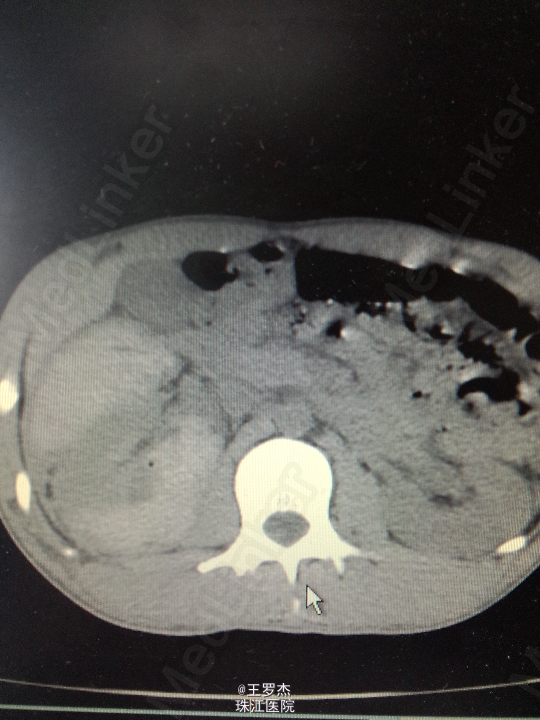

体格检查:体温:37℃,呼吸23次/分,脉率:84次/分,血压132/88mmHg。神情,查体配合。右季肋区可见3x4cm皮肤挫伤,腹部平软,双肾区无隆起,双侧输尿管走向无压痛,未触及包块,耻骨上区无充盈。 实验室检查:RBC 4.1,Hb 110g/L,WBC12.97,Cr187.0umol/L 辅助检查:CT右肾挫裂伤,包膜下大量积血,肾周、腹腔及盆腔内较多积液伴积血。

诊断治疗:右肾挫裂伤,保守治疗。3天后复查Hb89g/L,RBC2.65;复查CT提示包膜下及盆腔积血较前增多。请介入科会诊,行右肾动脉选择性栓塞。 介入:右肾挫裂伤,并上极动脉破裂出血及远端多处动静脉瘘形成,成功行超选择性病变血管栓塞术。